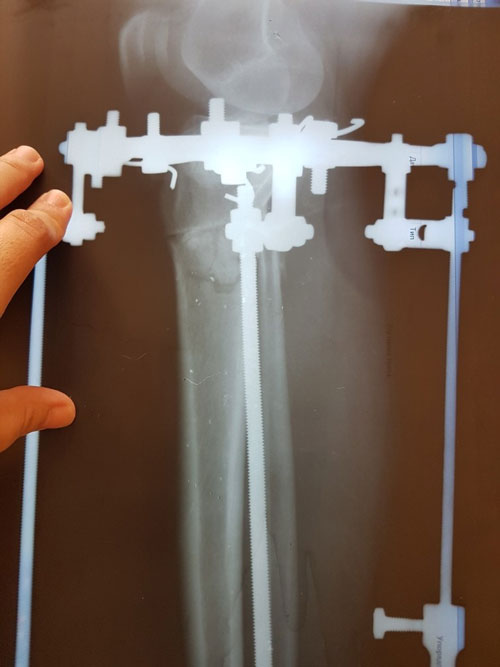

Дата операции 15.03.2017г.

Дата снятия аппаратов 23.06.2017г.

Срок лечения 97 дней.